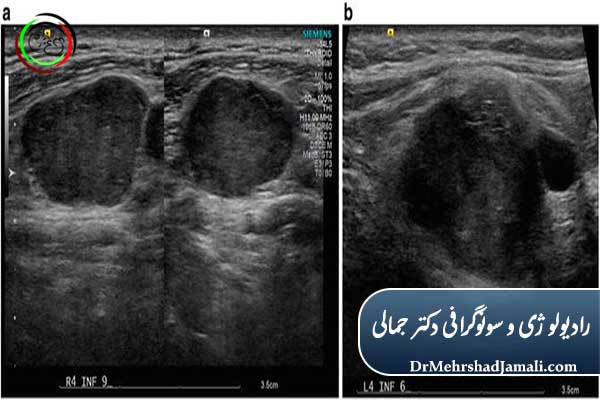

سونوگرافی گردن یکی از دقیقترین روشهای تصویربرداری برای بررسی تیروئید، غدد لنفاوی، غدد بزاقی، شریان کاروتید و انواع تودههای گردنی است. این روش به کمک امواج اولتراسوند انجام میشود، بدون درد، بدون اشعه و کاملاً بیخطر بوده و برای خانمهای باردار، کودکان و حتی بیماران خاص نیز قابل انجام است. وقتی بیمار دچار ورم، گلودرد مزمن، توده گردن، درد تیروئید، گرفتگی صدا، تغییر ناگهانی سایز گردن، یا مشکلات عروقی گردن شود، پزشک معمولاً اولین انتخاب را «سونوگرافی گردن» قرار میدهد.

در این بخش اندازه تیروئید، شکل لوبها، وجود ندول تیروئید ، کیست، التهاب یا کمکاری و پرکاری بررسی میشود. سونوگرافی بهترین روش کشف ندولهای تیروئید و تشخیص اولیه سرطان تیروئید است.

غدد لنفاوی در بیماریهای ویروسی، عفونتها، مشکلات سیستم ایمنی و گاهی سرطانها دچار تورم یا تغییر شکل میشوند.